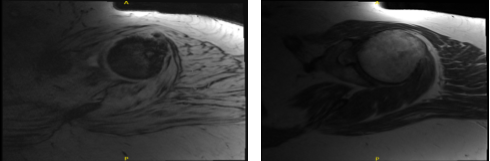

MRI Clavicle has been done and presented in the office. Acromion and bursa: The acromion has a curved configuration (type II). Moderate degenerative changes are present at the acromioclavicular joint. A small amount of fluid is present in the subacromial/subdeltoid bursa.

Rotator cuff tendons: Supraspinatus tendinosis present with high-grade partial-thickness articular sided tearing and a full-thickness component involving the anterior 2.2 cm of the distal supraspinatus tendon.

Infraspinatus tendinosis is present with high-grade partial-thickness articular sided tearing. Subscapularis tendinosis is also present with partial tearing at its insertion. Biceps tendons: There is no visualization of the long head of the biceps tendon, consistent with a complete tear and distal retraction.

Cartilage and labrum: Superficial cartilage irregularity is present in the glenohumeral joint. Degenerative tearing of the posterosuperior glenoid labrum is present. Bone marrow:

Subchondral cyst formation is present on the posterior aspect of the greater tuberosity. The bone marrow signal is overall age appropriate.

There is no evidence for significant lymphadenopathy in the visualized portions of the axilla. No asymmetric rotator cuff muscle atrophy is present. We decided to do another MRI to run more tests about her shoulder.

MRI first result